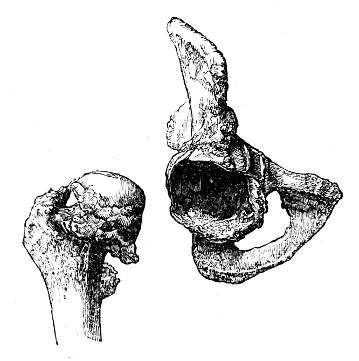

| Coxalgia | 81 |

| Alterations of Form in the Head of the Femur | 86 |